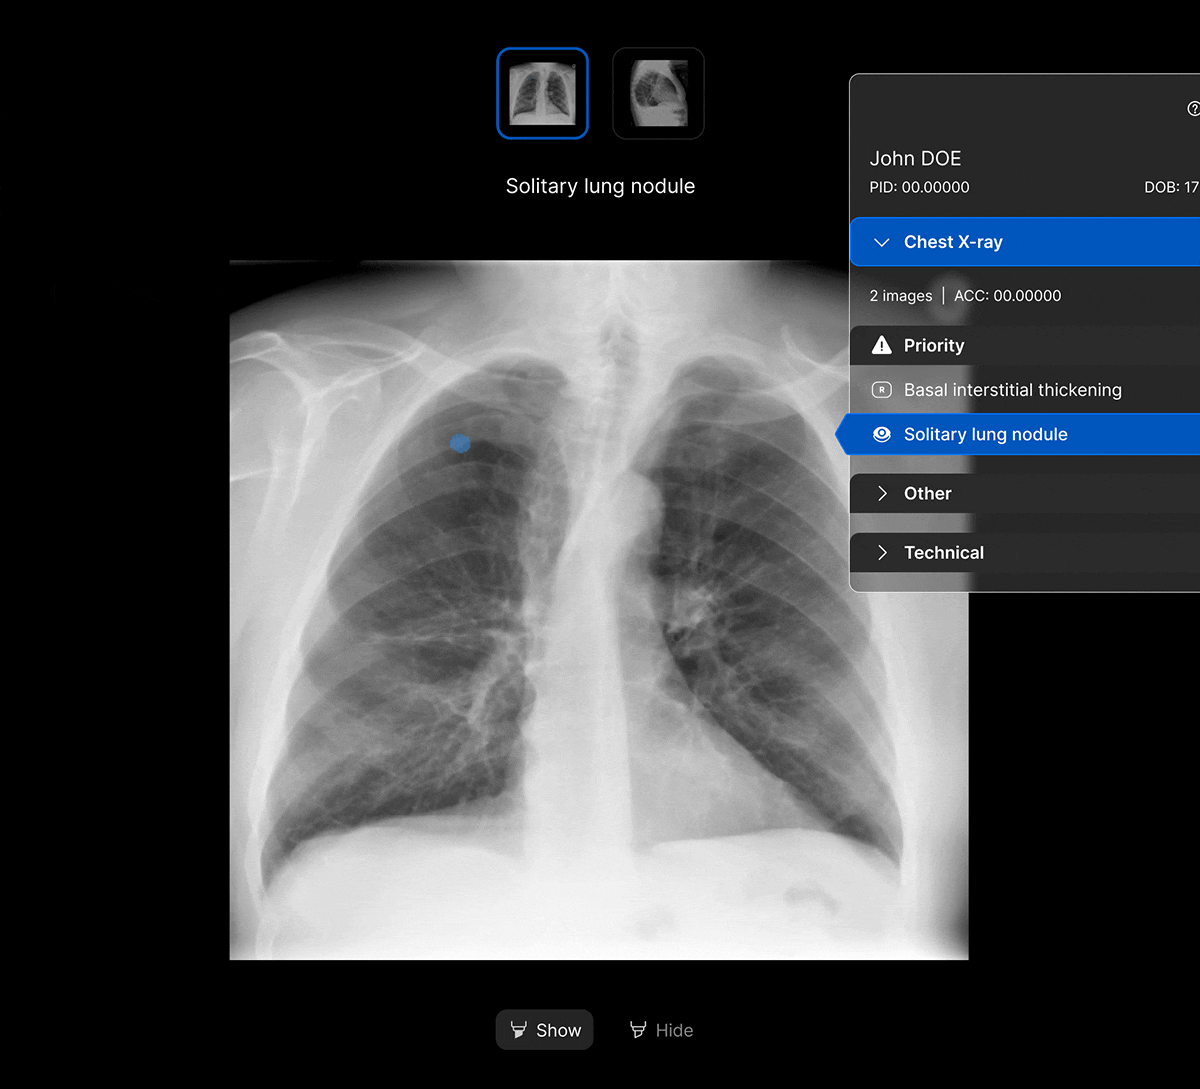

Seamless workflow.

The UI integrates seamlessly with PACS/ RIS, displaying a resizable, no-click overlay window with findings and localisation.

Optimise your worklist, prioritise what matters.

Accelerate care pathways with AI-powered Worklist Prioritisation. Detect up to 124 findings on chest X-ray, enabling optimised workflows across multiple use cases and care settings including radiology, emergency and acute care, lung cancer pathway, chronic care and teleradiology.

- Customisable clinical findings and thresholds to suit your workflow.

- Seamless integration with PACS and RIS.

One CXR solution. Powerful clinical value.

Our comprehensive range of 124 clinical findings for chest X-ray means you can benefit from powerful clinical impact and value across multiple use cases and healthcare settings.